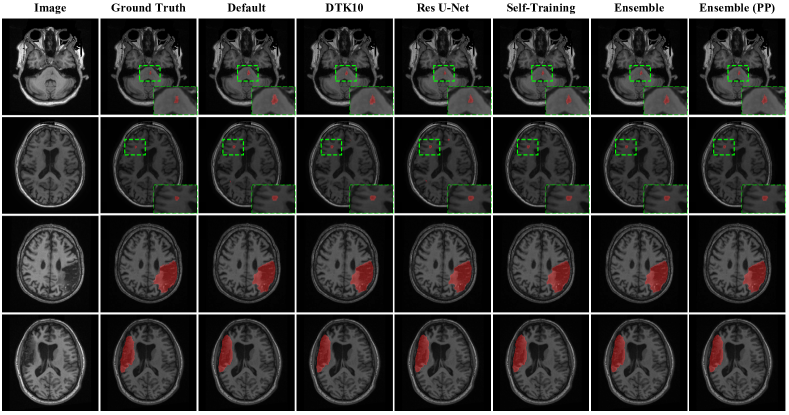

3.7 Failure Analysis

We also show four failure cases in Fig. 6, where the different training schemes are unable to segment the lesion area accurately, or even give foreground predictions. The top three cases in Fig. 6 indicate that our models still can not segment small stroke lesions well in some scenarios, especially where the scans are with artifacts (the first row), or the lesion intensity is similar with surrounding areas (the second and third row). Finally, the bottom case reveals that all training schemes tend to predict unconnected lesions as a continuous lesion, especially confusing grey matter and lesion areas due to the similarities in their intensities.

Refer to caption

Figure 6: Qualitative analysis of four failure cases. The top three rows show small lesions where the different training schemes are unable to segmentation foreground voxels due to image artifacts and poor image contrast between foreground and background. The bottom row shows several unconnected lesion regions, where the different training schemes are oversegmenting the lesion to connect the regions.